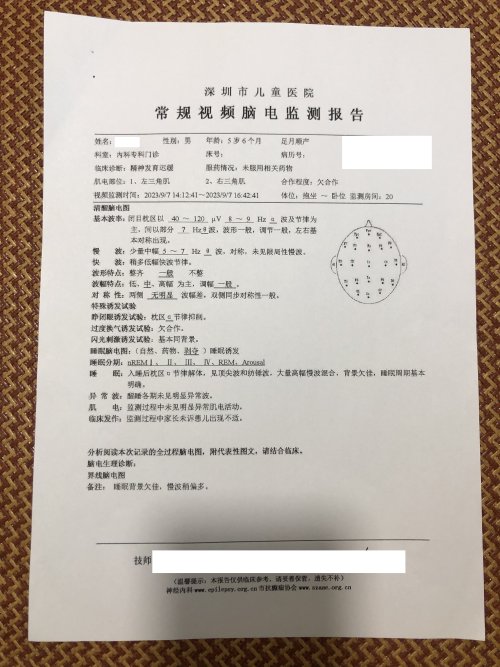

反馈下情况,孩子在国内的医院已经进行过一轮全面检测,没发现什么问题,但是现象是存在的。医生也没什么办法。医生说核磁共振和脑电图没问题,我们也不是很看得懂,各位如果懂的,请指点一下。另外进行了部分基因检测,没发现异常。下一步,我们国庆后打算去更权威的医院去碰碰运气。谢谢各位!

513.6 KB 查看: 103

532.8 KB 查看: 142

551 KB 查看: 132

526.8 KB 查看: 133

510 KB 查看: 103

506.4 KB 查看: 124

495.7 KB 查看: 165